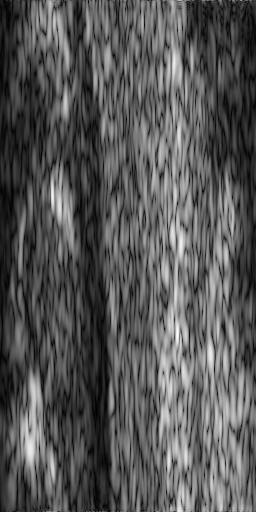

Figure 2: Ultrasound images (a) 1, (b) 2, (c) 3, (d) 4, (e) 5 and (f) 6 from set 1

The first set of images we use to test these methods come from the same dataset as those used in [33]. The data corresponds to in vivo healthy thyroid glands. The images were acquired using a Siemens Sonoline Elegra scanner using a 7.5 MHz linear probe and a sampling frequency of 50MHz. Each of the 7 images we use for testing were acquired by cropping patches of size 512×256512256512\times 256 from the original images. That is, the images consist of 256 lines, each of length 512.

Figure 3 shows Image 1 after being subsampled at 50% and then recovered with various algorithms. Figure 4 shows the same for Image 2 after it was subsampled at 33%.